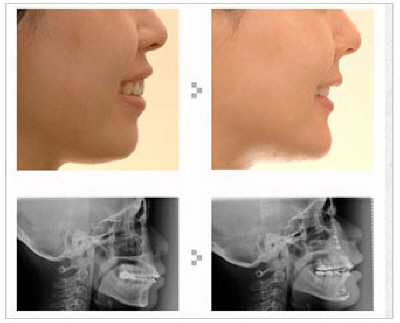

‘돌출입’이란 얼굴을 옆에서 보았을 때 코끝이나 턱 끝에 비해 입이 앞으로 더 튀어 나온 모양을 하고 있다. 입술 끝이 콧구멍 높이의 중간보다 높거나 코끝보다 높게 보이는 게 특징이다. 마치 입으로 바람을 불 때와 같은 모양을 하고 있어 미관상 좋지 않다.

돌출입 교정수술인 양악수술에 관심이 있다면 우선 양악수술에 대해서 알아둘 필요가 있다. '양악'이라는 말은 '두 양'에 '턱 악'자가 합쳐진 한자어로 두 턱, 즉 위턱 아래턱 수술이라는 뜻이다. 즉 치아가 포함된 위턱뼈와 아래턱뼈의 위치를 바꿔주는 수술이다. 위턱의 뒷부분은 넣어주면서 뒤로 이동시키고 아래턱은 위로 넣어주면서 뒤로 이동시키게 되는 두 가지 방법이 복합된 수술을 말한다.

양악수술은 얼굴의 절반 정도를 뒤로 밀어주게 되므로 얼굴이 드라마틱하게 작아지면서 완벽한 V라인을 만들어 준다. 미용 목적의 양악 수술은 수술 전 교합이 정상일 경우 수술 전 교정은 물론 치아 발치도 필요 없다. 수술 준비로 기다려야 하거나 치과 치료를 할 필요도 없어서 편리하다는 장점이 있다.